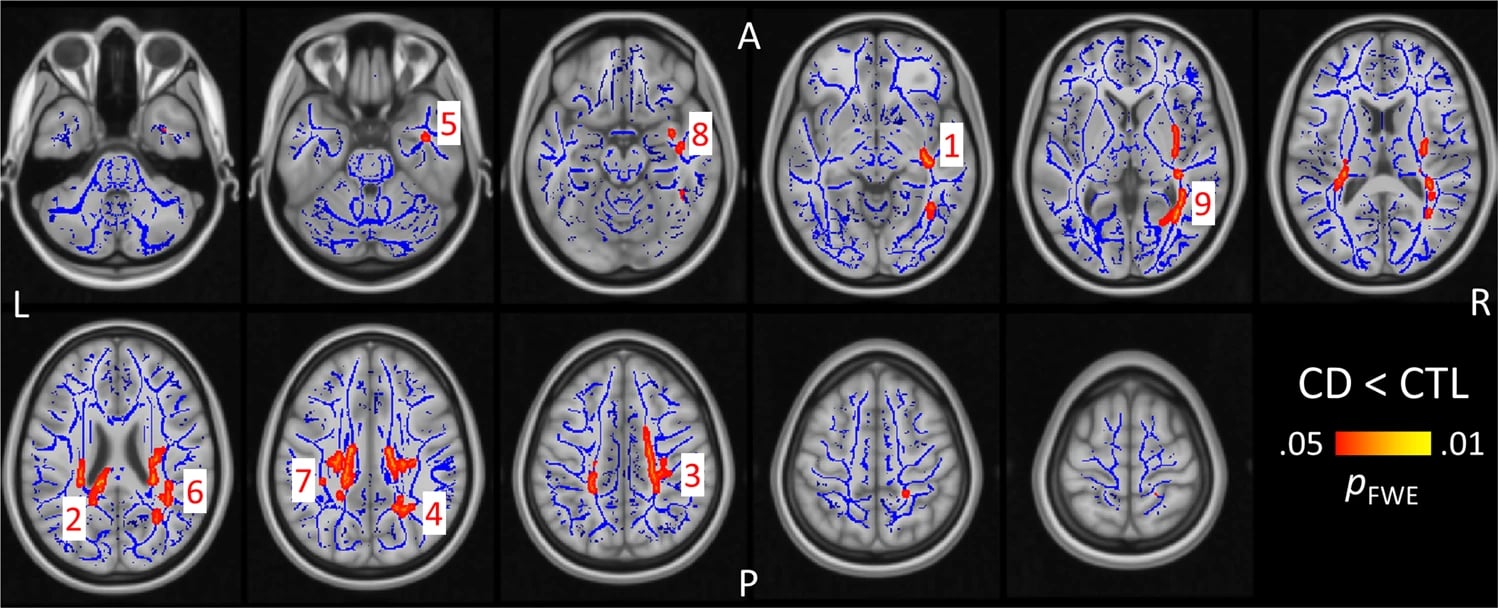

According to the Centers for Disease Control and Prevention (CDC), cannabis use impacts key areas of the brain responsible for memory, learning, attention, decision-making, coordination, and emotions. These effects are particularly concerning when use begins during adolescence, a critical period of brain development.